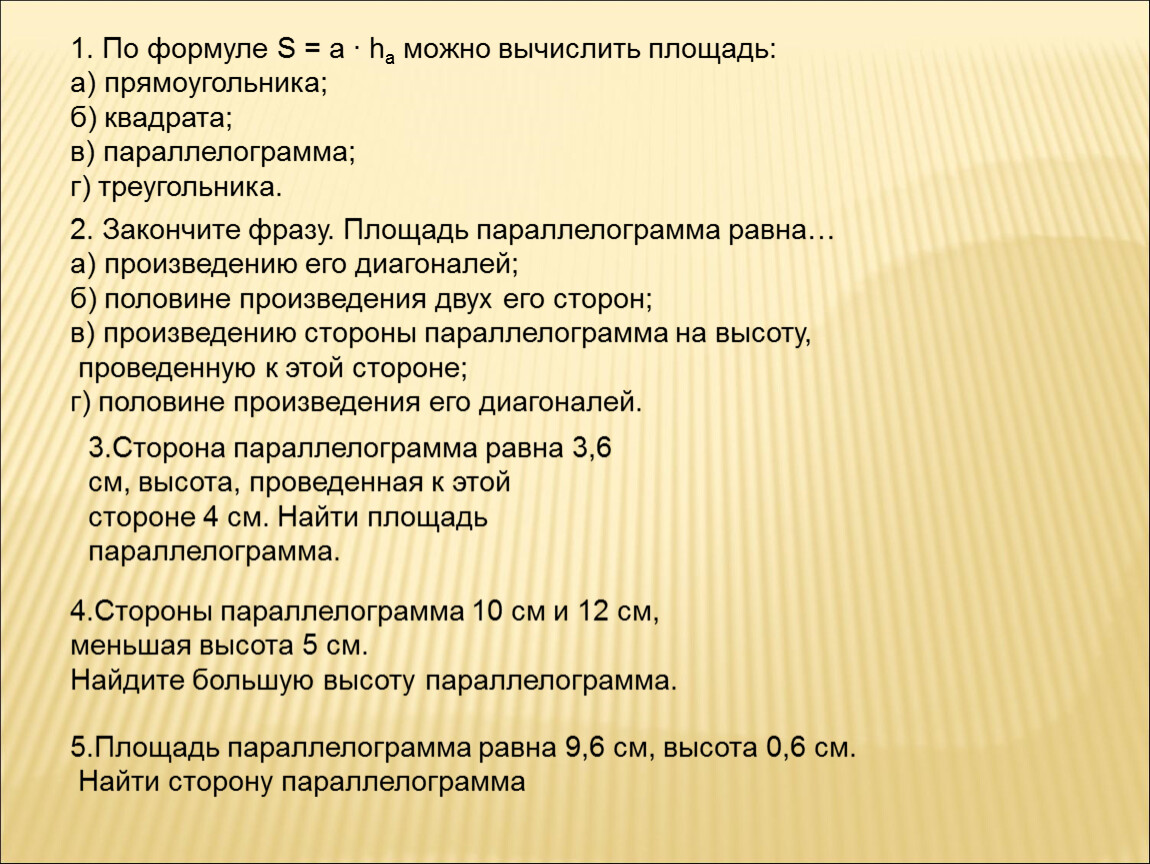

Код мкб 10 атерома головы

Код мкб 10 атерома головы 109 фото